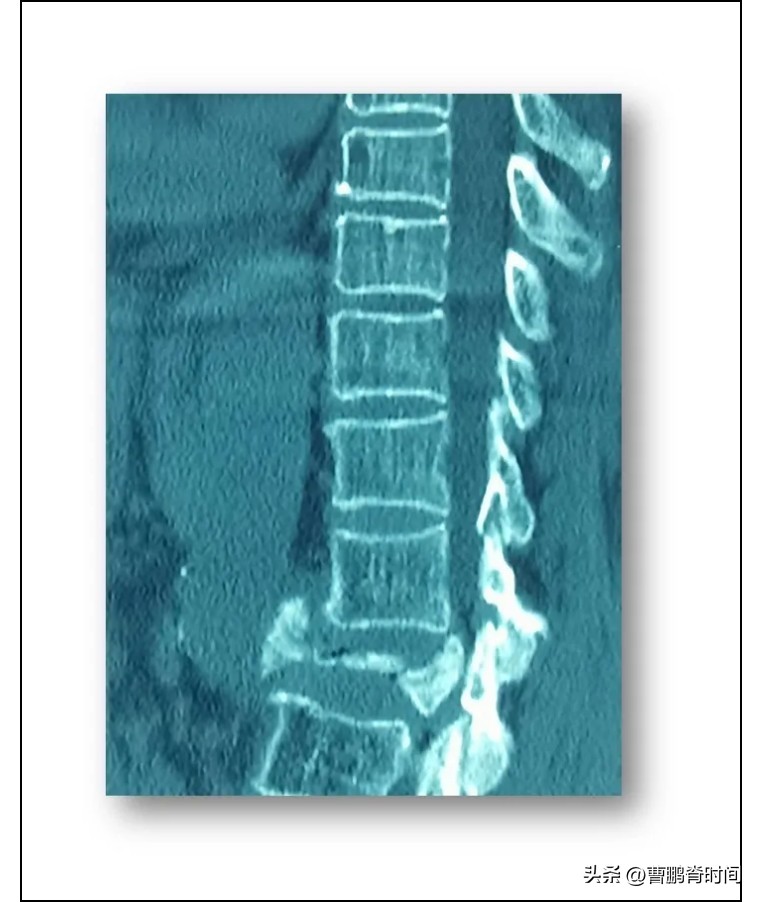

根据周女士的病例报告显示:她的腰椎第二节被完全 砸扁 。

据她描述是在一次跳绳后,腰部突然传来剧痛,并伴随 下肢发麻 。

虽然周女士半年前才经历的乳腺癌手术为这次 腰椎固定 与 修复 手术增加了挑战,手术还是十分成功。

术后周女士的腰痛和下肢麻木都得到了有效的改善,也并未产生其他任何不适。